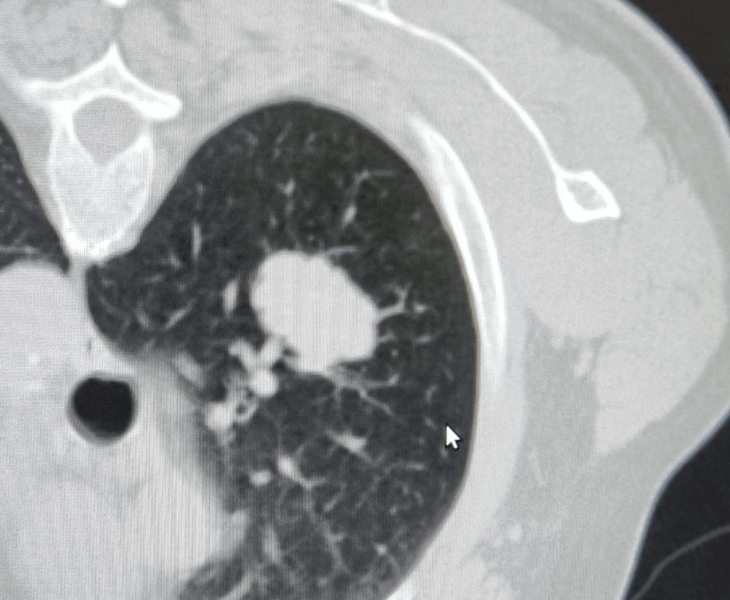

Lung & Mediastinal Biopsies

CT‑guided biopsies for suspected lung/mediastinal tumours and nodules.